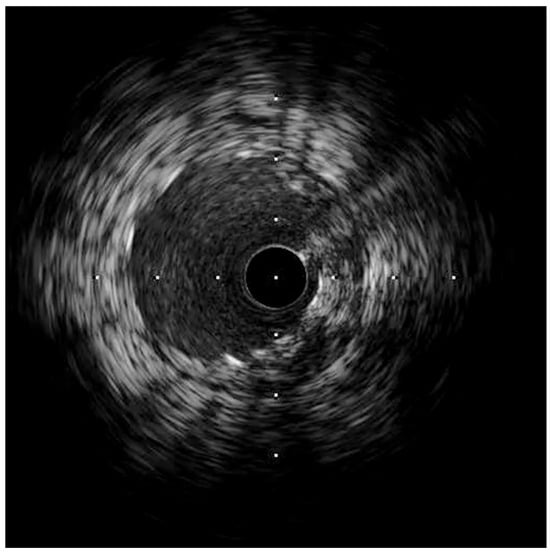

- Case # 1